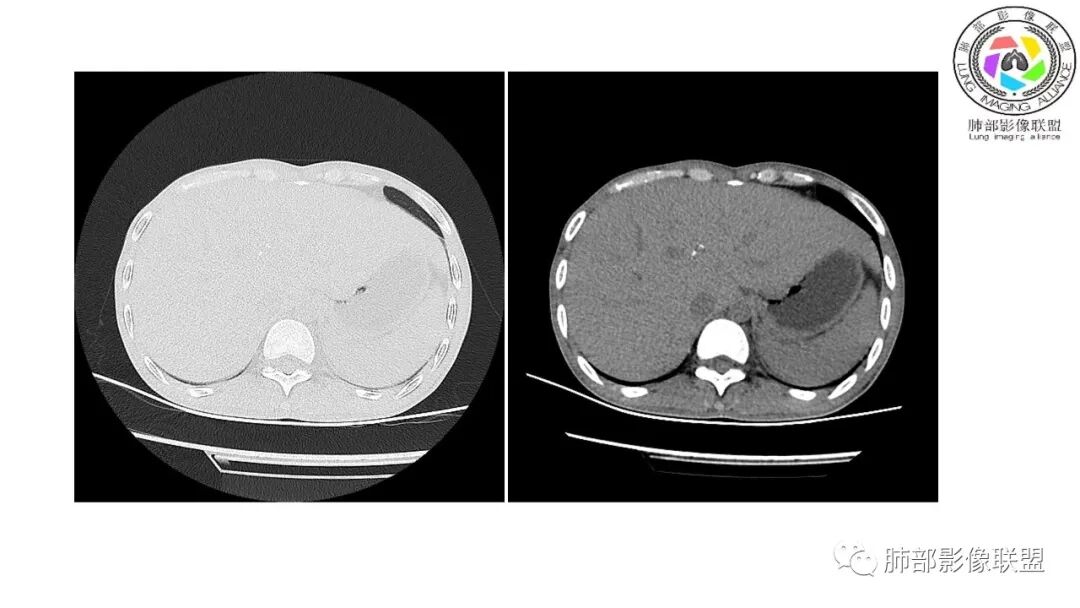

以下为2021-7-15日上腹部CT

影像与临床:1.青年男性,HlV阳性,颜面部皮疹(未提供皮疹图像)、发热(高热),实验室CRP、PCT高,T-Spot阴性。2.右肺下叶空洞结节,壁厚不均,边界清楚,其内线状影,未见液平及钙化,未见卫星灶,纵隔淋巴结增大,双侧腋窝见增大淋巴结。心腔内低密度提示贫血可能。肝脾影增大,未见结节影及块影。腹膜后见多发增大淋巴结。

综合分析:本例肺部影像学改变并不具有特征性,空洞性病灶须与多种疾病鉴别,但年轻HIV阳性患者,高热,皮疹,肝脾增大,纵隔、腋窝、腹膜后见多发增大淋巴结等都强烈提示马尔尼菲篮状菌感染的可能性。